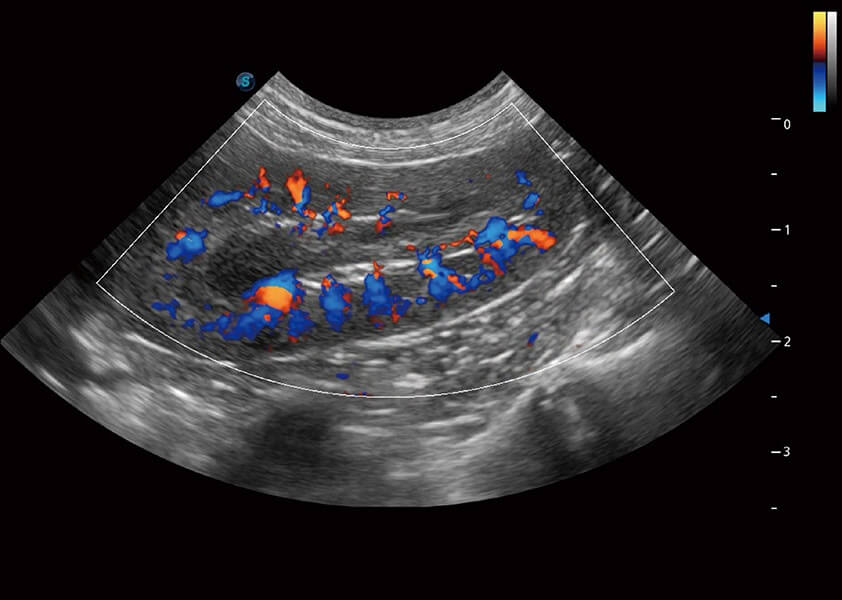

ProPet 60 作为一款高端台式动物超声设备,为动物医生的日常诊断提供了一系列贴合动物临床需求、解决临床实际问题的高级成像功能。凭借全系列高清探头,满足医生对腹部、心脏、生殖、浅表、肌骨等成像的所有需求,切实帮助您提升检查效率,提高诊断信心。

动物是人类最亲密的朋友和最值得信赖的伙伴。16877太阳集团也一直致力于探索动物专用的超声影像解决方案。 全新推出的ProPet系列,是16877太阳集团在动物超声影像智能化、专业化、精准化的一次跨越式革新。动物不能用言语来表述自己的不适,通过超声影像,ProPet系列搭建了动物医生与不同物种沟通的“桥梁”,为动物医生注入了“治愈之力”。